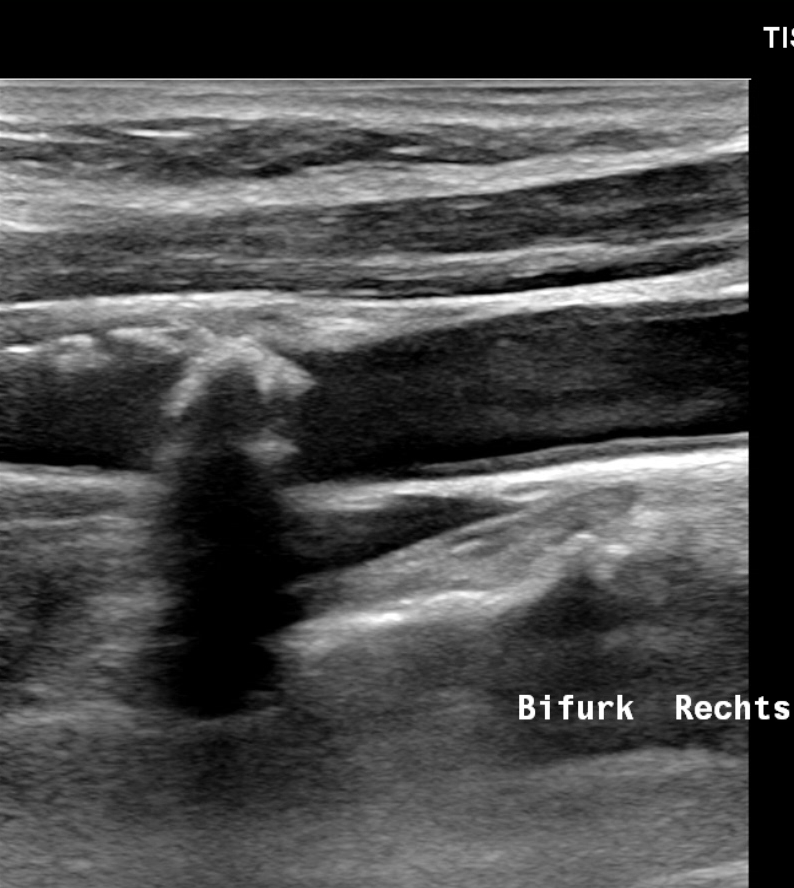

An dieser Gabelung teilt sich der Blutstrom Richtung Gehirn und Gesicht. Hier entstehen statistisch die meisten Ablagerungen.